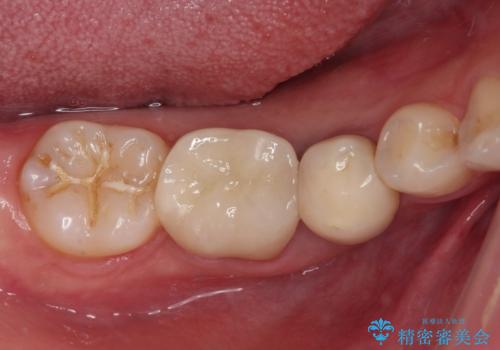

奥歯は抜歯をせずに保存することができました。ただし、状態は決して良いとは言えないため、定期的に経過を見ていく必要があります。